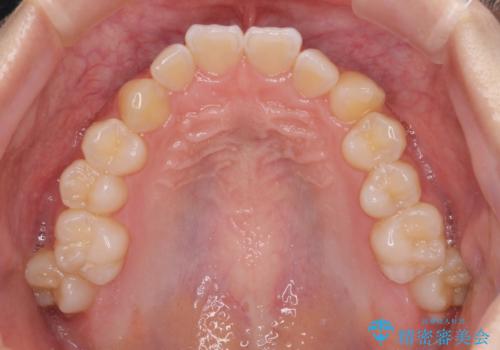

- 前歯のデコボコと磨きにくい奥歯を気にして来院された患者様です。

左右ともに上顎第二大臼歯が外側に転位しており、大変磨きにくくなっているため、補助装置により内側に引き込むことで改善することとしました。

外側を向いていた奥歯は比較的早い時期に歯列に収まり、咬み合わせも磨きやすさも改善することができました。

歯列は元々悪くなかったので、1年ほどで治療を終えることができました。